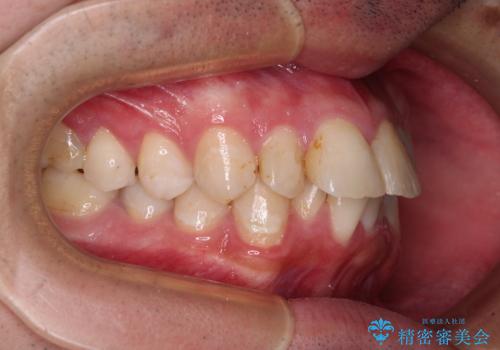

- 口元の突出感と奥歯の咬み合わせの悪さを気にして来院された患者様です。

口元はやや突出感があったため、上下左右の第一小臼歯4本を抜歯してワイヤー矯正にて抜歯矯正を行うこととしました。

また、左右ともに最後臼歯が交叉咬合になっており、外側に飛び出している上顎の最後臼歯を補助装置を利用して、積極的に内側に引き込むようにしました。